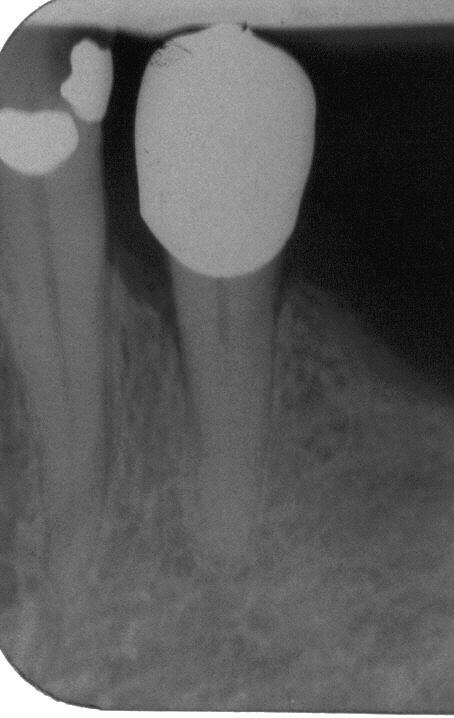

WF Kontrollaufnahme

WF Kontrollaufnahme im Dez. 2001. WF in lateraler Kondensation mit genormter Guttapercha und AH 26. Der linguale Kanal war nicht weiter erschließbar

WF Kontrolle

WF Kontrolle ein Jahr später im Dez. 2002